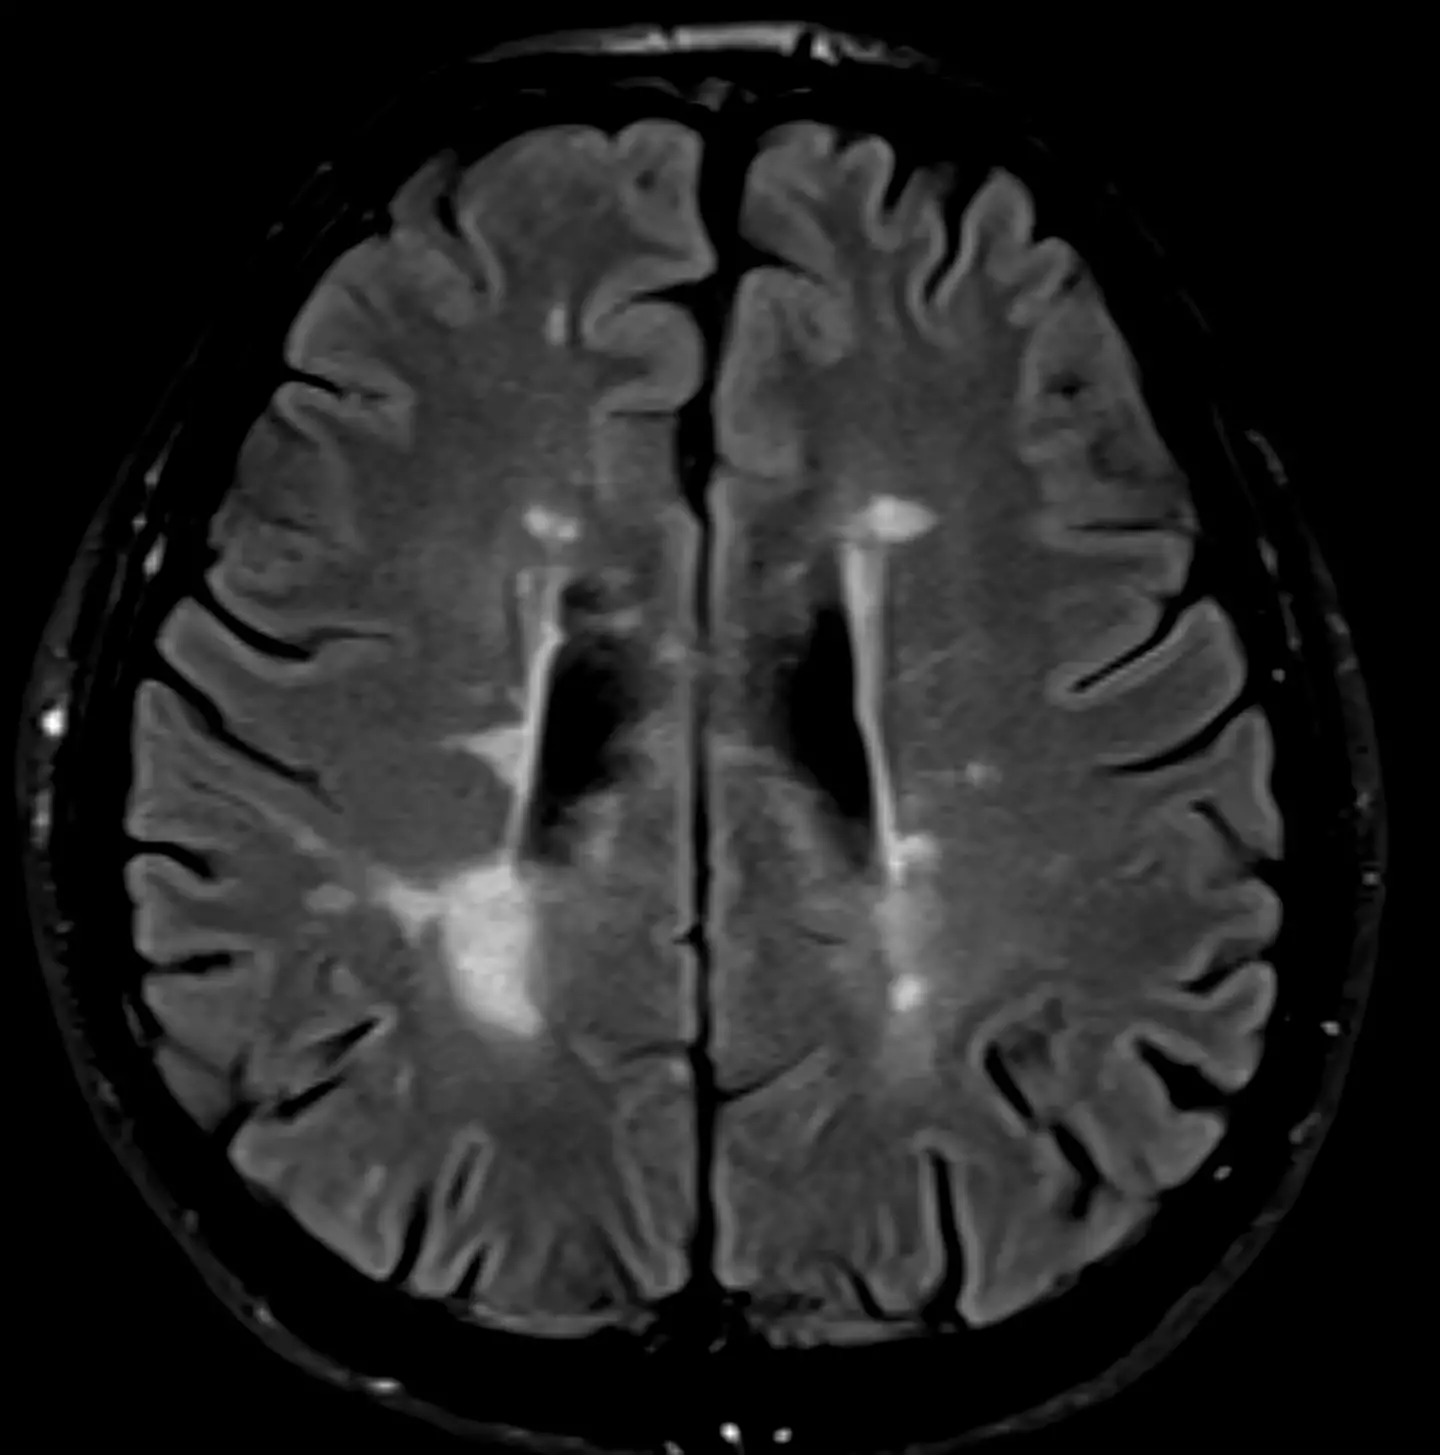

The disease is caused by your immune system attacking the brain and nerves for a reason that remains unknown, meaning it cannot be cured (though medicines and other treatments can help ease symptoms).